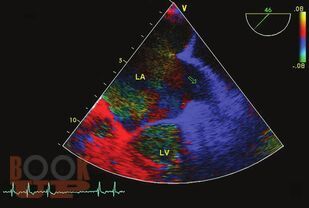

Книга посвящена одной из актуальных проблем кардиологии—тромбоэмболическим осложнениям у больных с аритмиями. Подробно обсуждаются молекулярные и генетические механизмы тромбообразования при аритмиях, клинические и инструментальные признаки внутрисердечных тромбов, а так же способы их визуализации. Приводятся данные о способах оценки риска тромбоэмболических осложнений и тактике антитромботической терапии в различных группах больных с аритмиями. Отдельно освещаются вопросы антитромботической терапии в сложных клинических ситуациях — при хирургических операциях, в случае обострения ИБС, при беременности, при проведении катетерной деструкции. Поводом для выхода второго издания книги послужило появление представителя нового класса антитромботических средств — дабигатрана этексилата, в связи с чем международное кардиологическое сообщество поменяло рекомендации по профилактике тромбоэмболических осложнений у больных с аритмиями. Для кардиологов (в том числе интервенционных), терапевтов, студентов медицинских вузов.